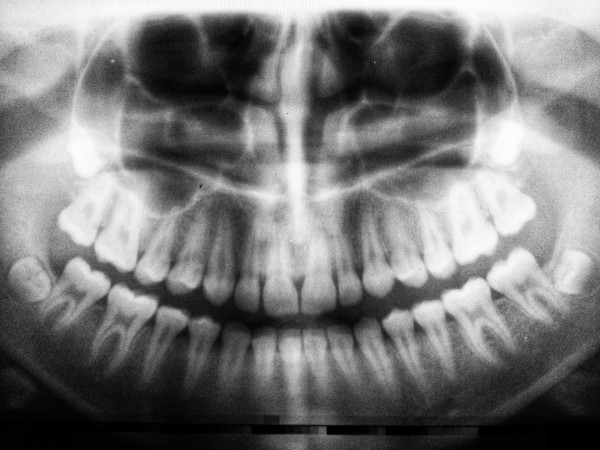

過剰歯は八重歯以外にも歯列に多くの悪影響を及ぼすため、歯列に違和感がある方は歯科医院でレントゲン写真を撮ってもらうと良いでしょう。